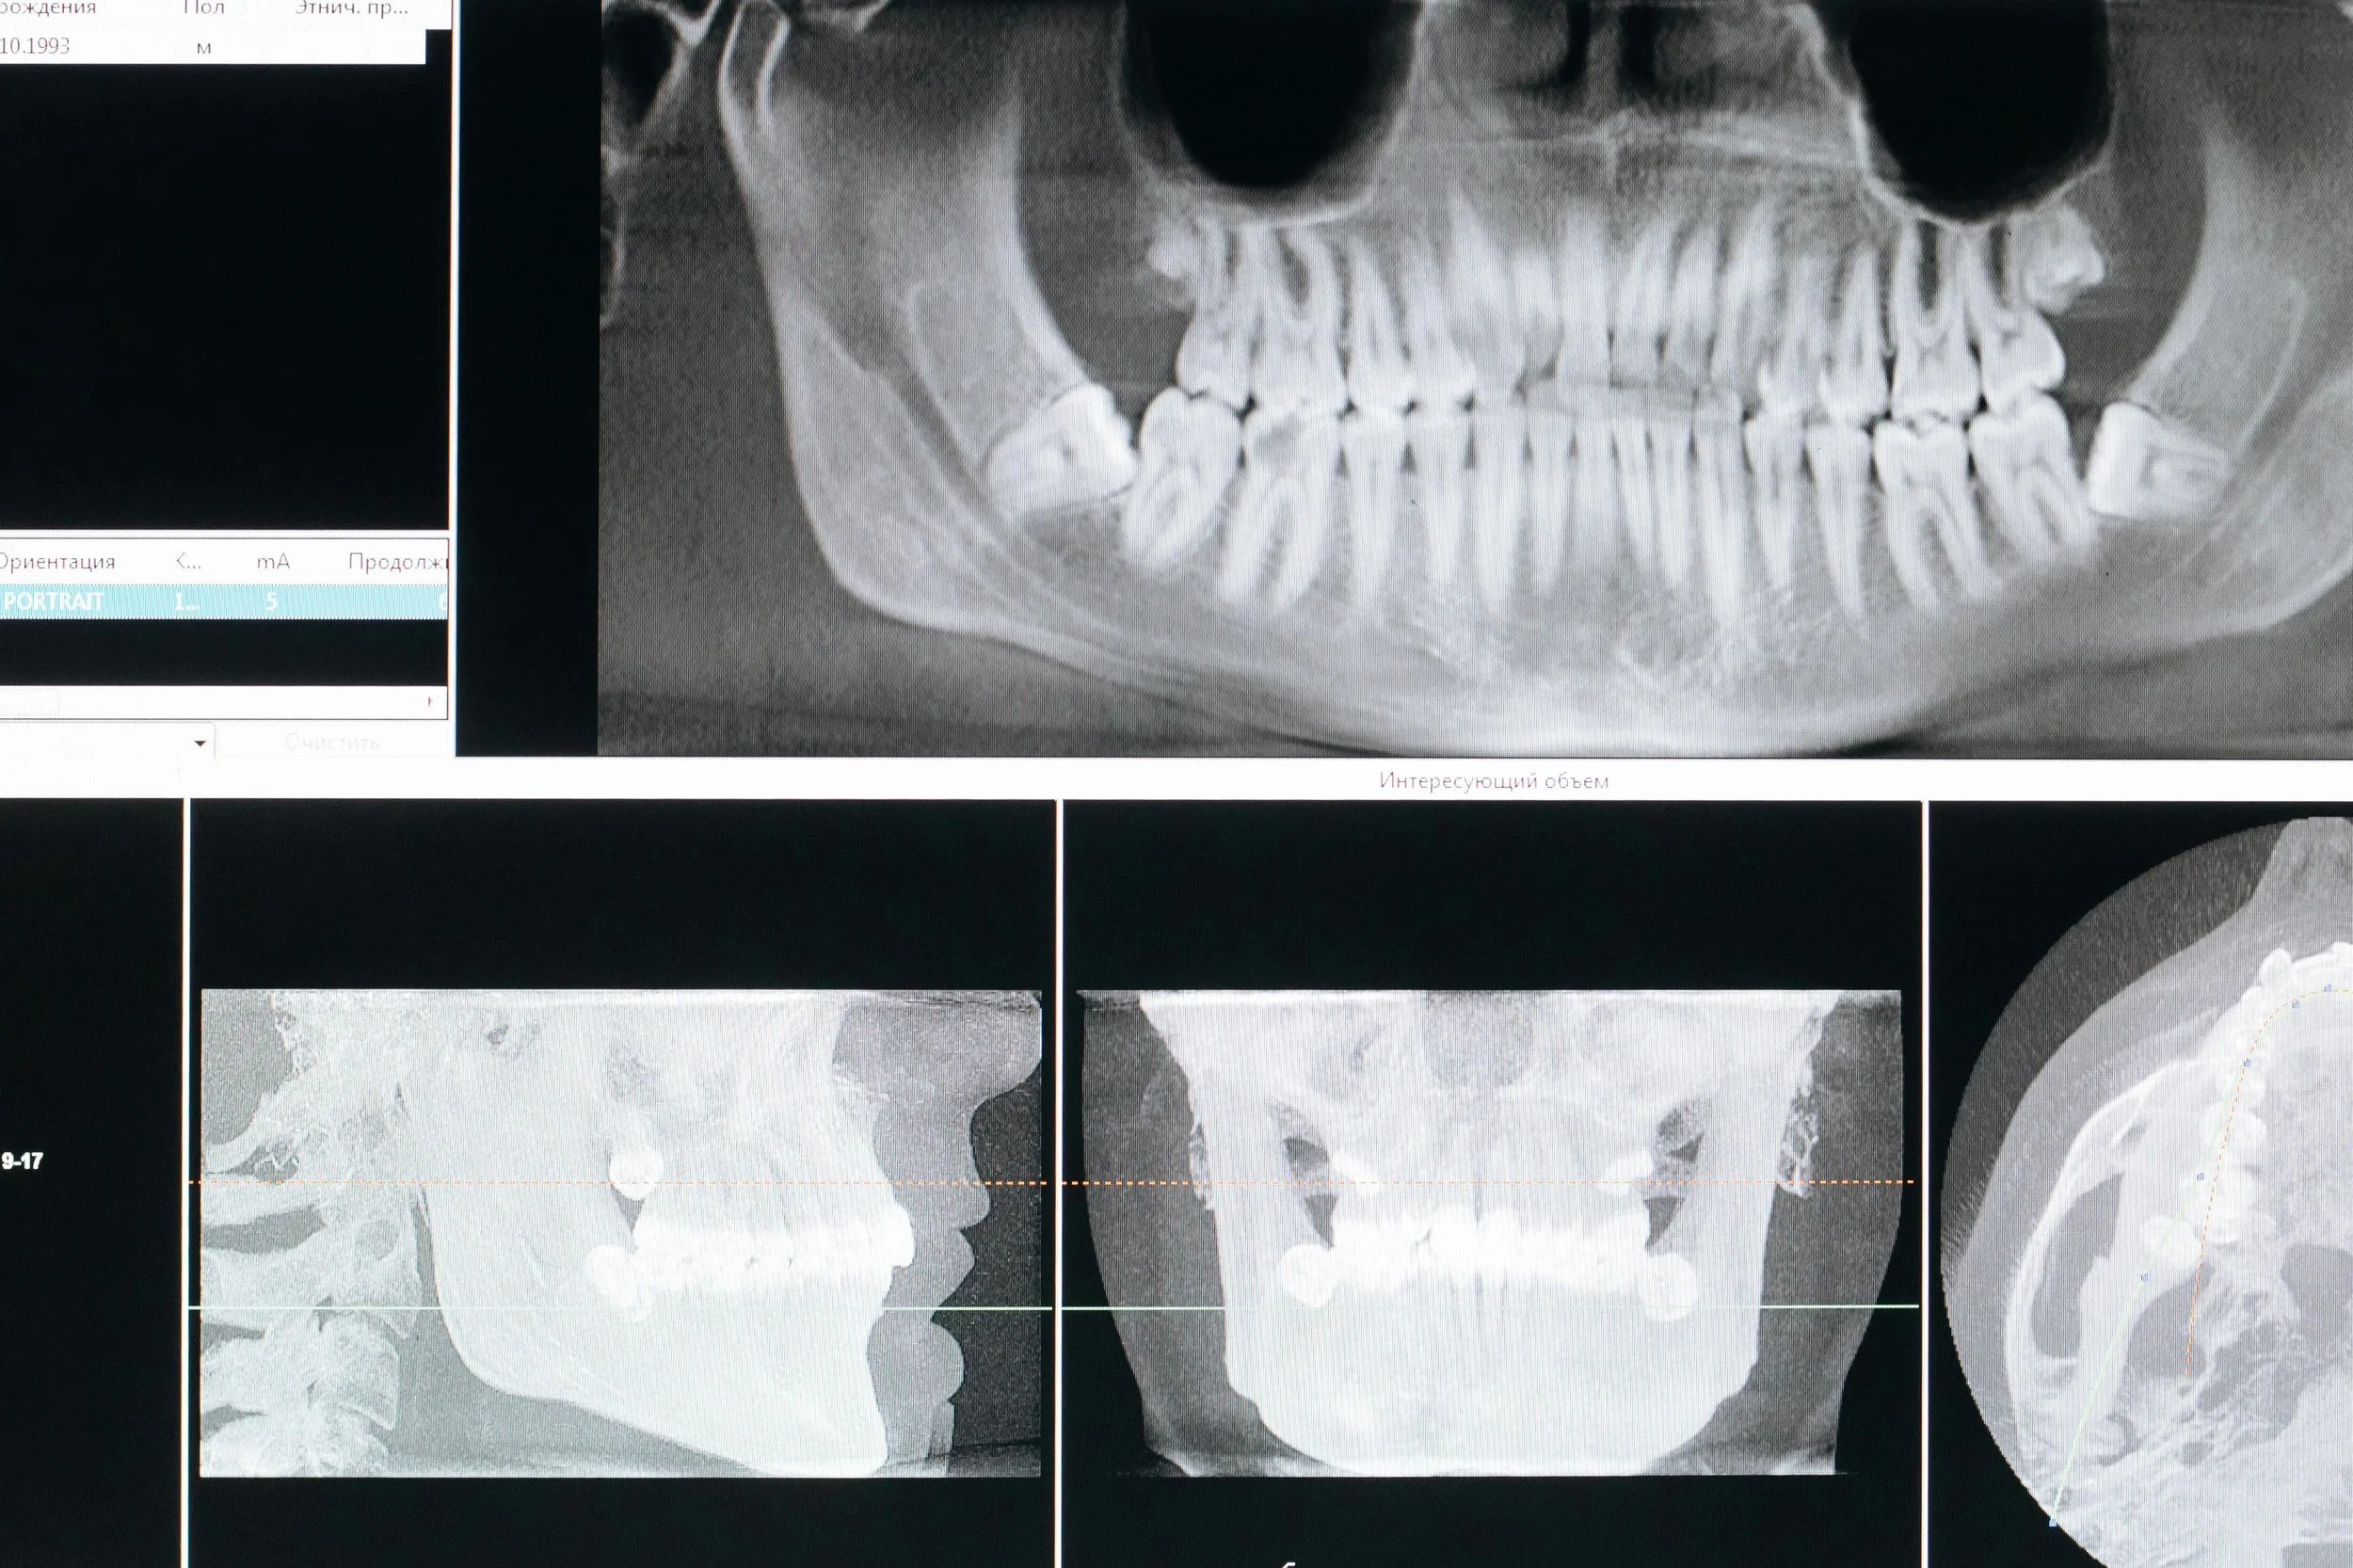

When you arrive, you’ll check in at the front desk before being escorted to take initial screening X-rays. Both the consultation with Dr. Griffies and these X-rays are complimentary—no fees are involved. You’ll also have the chance to meet our caring staff, get to know our office, and learn more about the treatment options available to you.